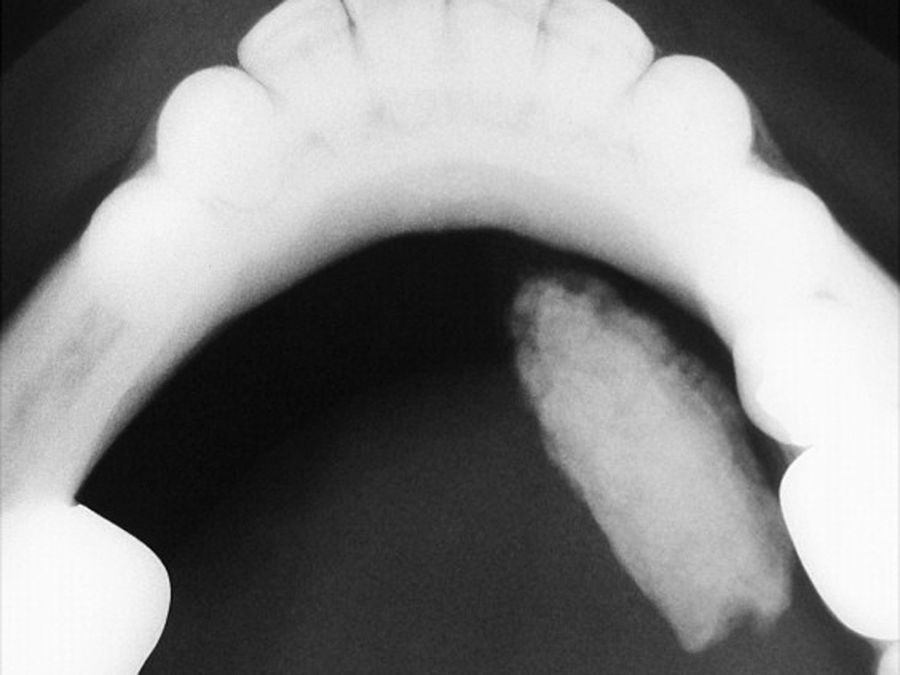

Foi solicitada uma radiografia oclusal da mandíbula, na qual se observou a presença de uma massa radiopaca cilíndrica e alongada na região correspondente do ducto da glândula submandibular do lado direito (fig. 2). Com base na história clínica e no achado radiográfico, estabeleceu-se o diagnóstico clínico de sialolitíase.